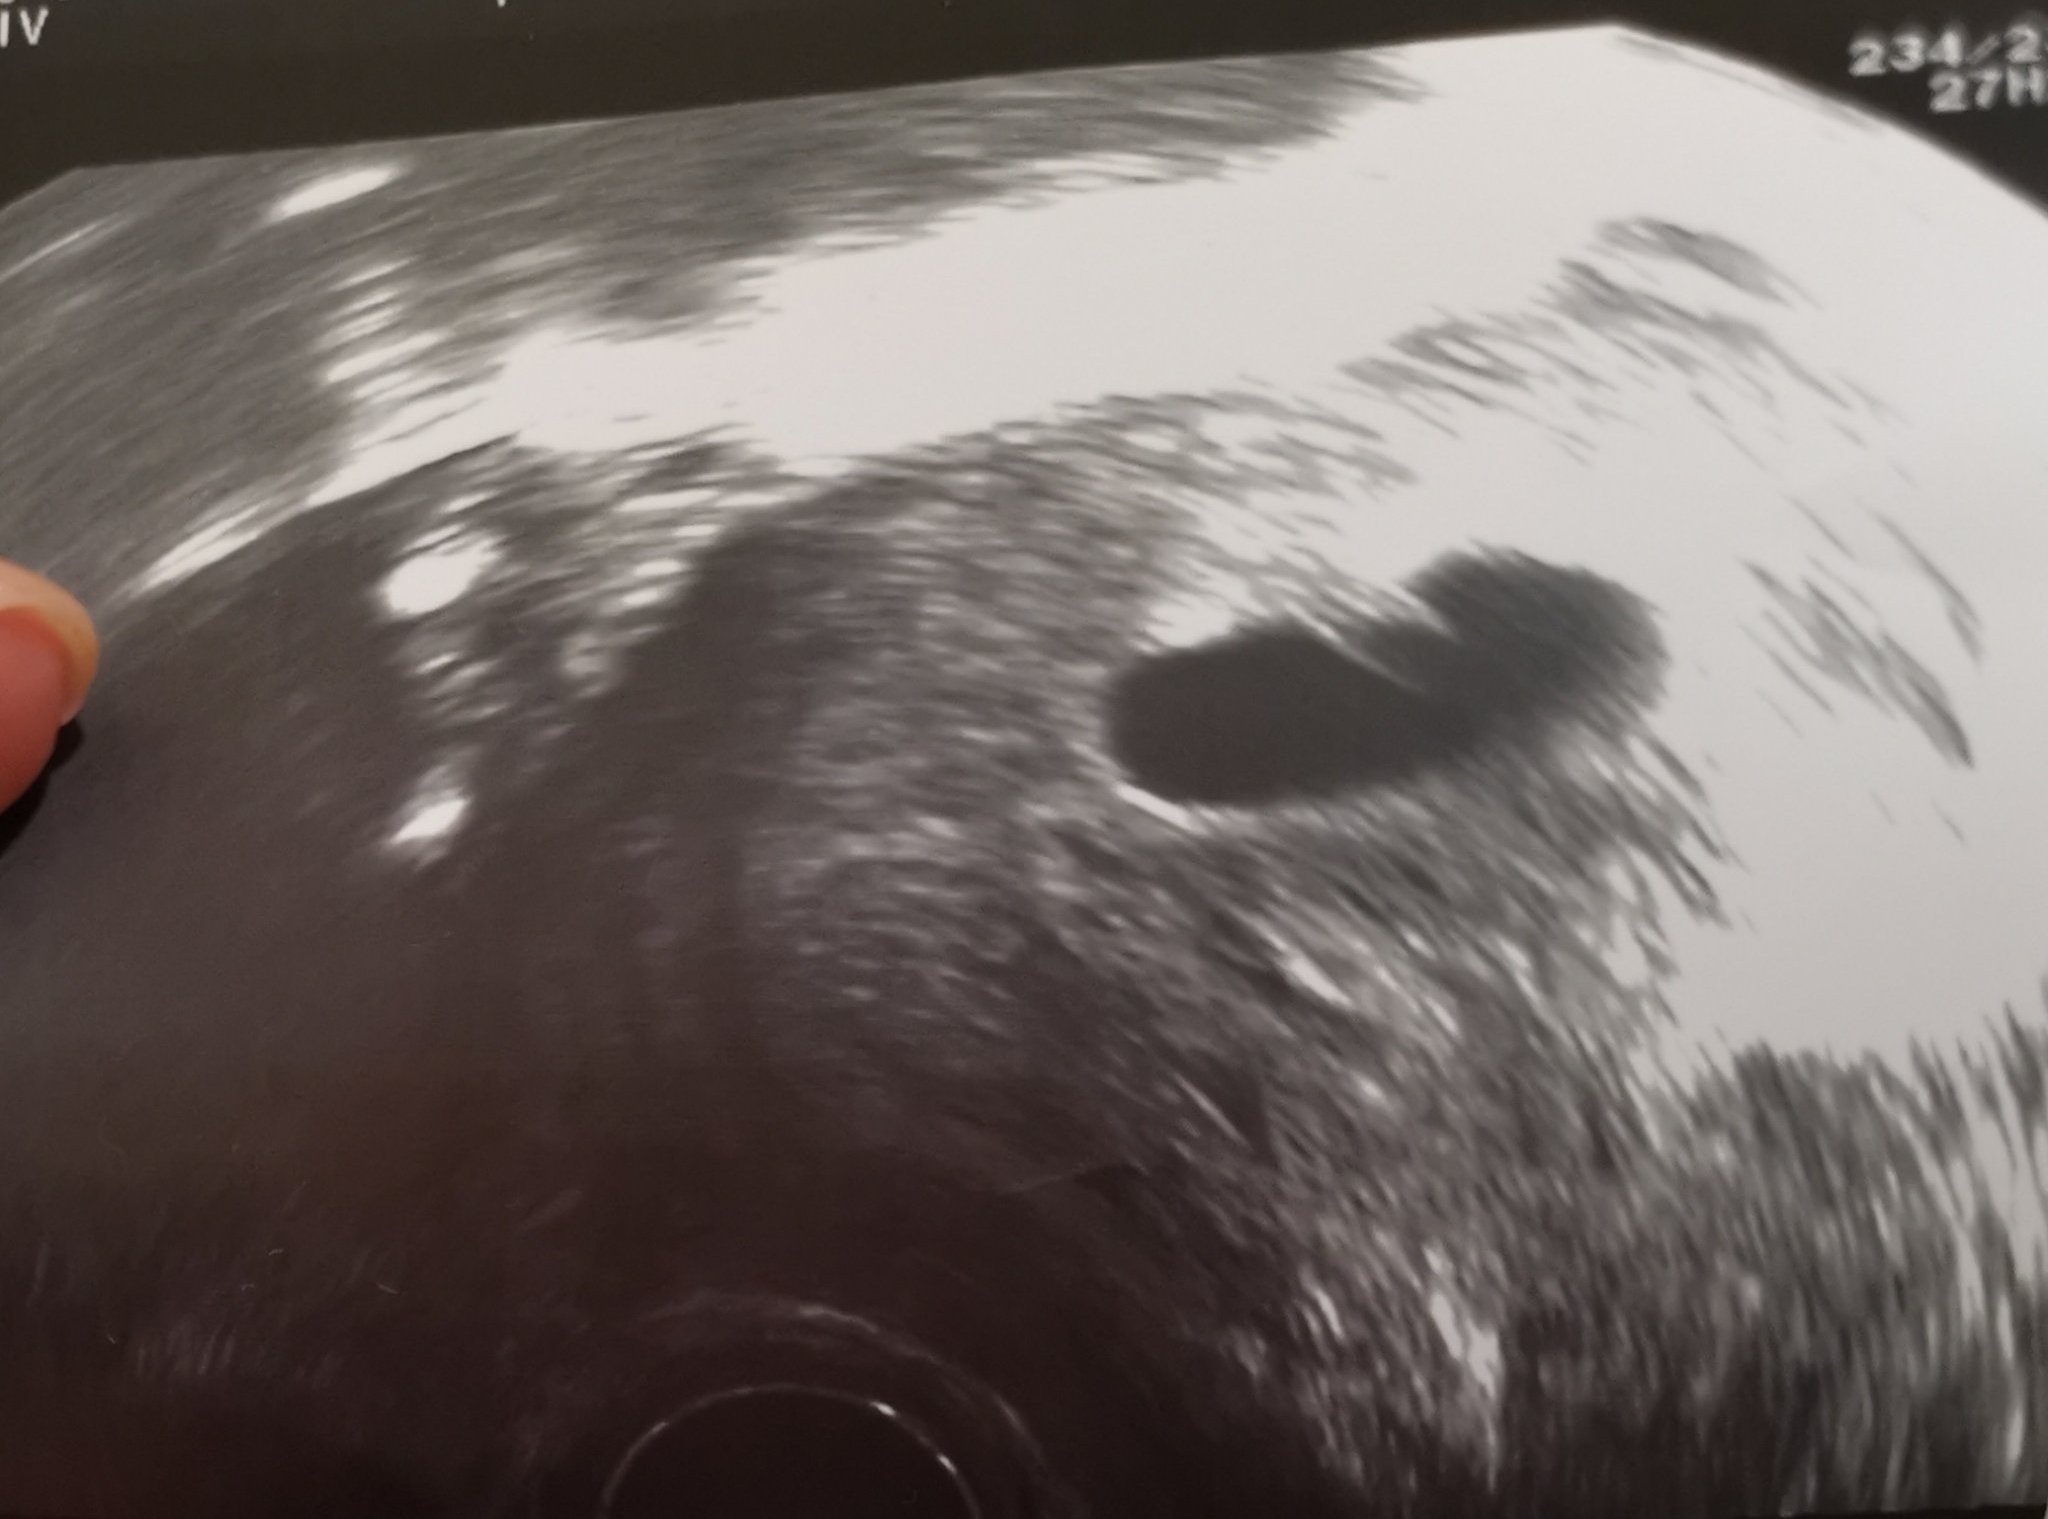

Кървенето по време на бременност може да се прояви с леки коремни болки и различни нюанси на кръвоизливи - блед розови петна върху ежедневната превръзка и тъмно кафеви нишки върху хартията. Това може да е признак за кървене, което обаче може да бъде безвредно. Важно е да се консултирате с лекар, за да сте сигурни в здравето на бебето и да получите необходимите насоки за грижи по време на бременност. Симптомите на ранна бременност могат да включват болезнености в гърдите, гадене, повръщане, повишена чувствителност към миризми, умора, често уриниране, кафяви петна по бельото и коремни и кръстни болки. Всички тези симптоми са обичайни и могат да варират от жена на жена.

При кървене по време на бременност е изключително важно да се консултирате с лекар за оценка на ситуацията. Вашият лекар може да предложи пълна почивка и допълнителни тестове, като например вливания или лекарства за поддържане на бременността. Важно е да следвате инструкциите на вашия лекар и незабавно да се свържете с него, ако имате някакви симптоми или притеснения.